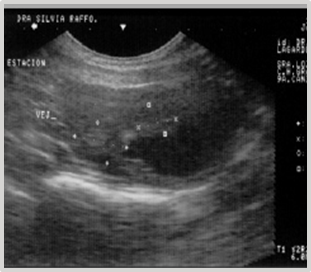

Evolution: The patient's progress occurs without significant clinical signs, except for mild hematuria. Symptomatic and ultrasonographic follow-up at 4, 6 months, and 1 year shows no recurrences (Figures 24) (Figure 25).

Figure 25 Ultrasonographic follow-up at 6 and 12 months post-cryosurgery.